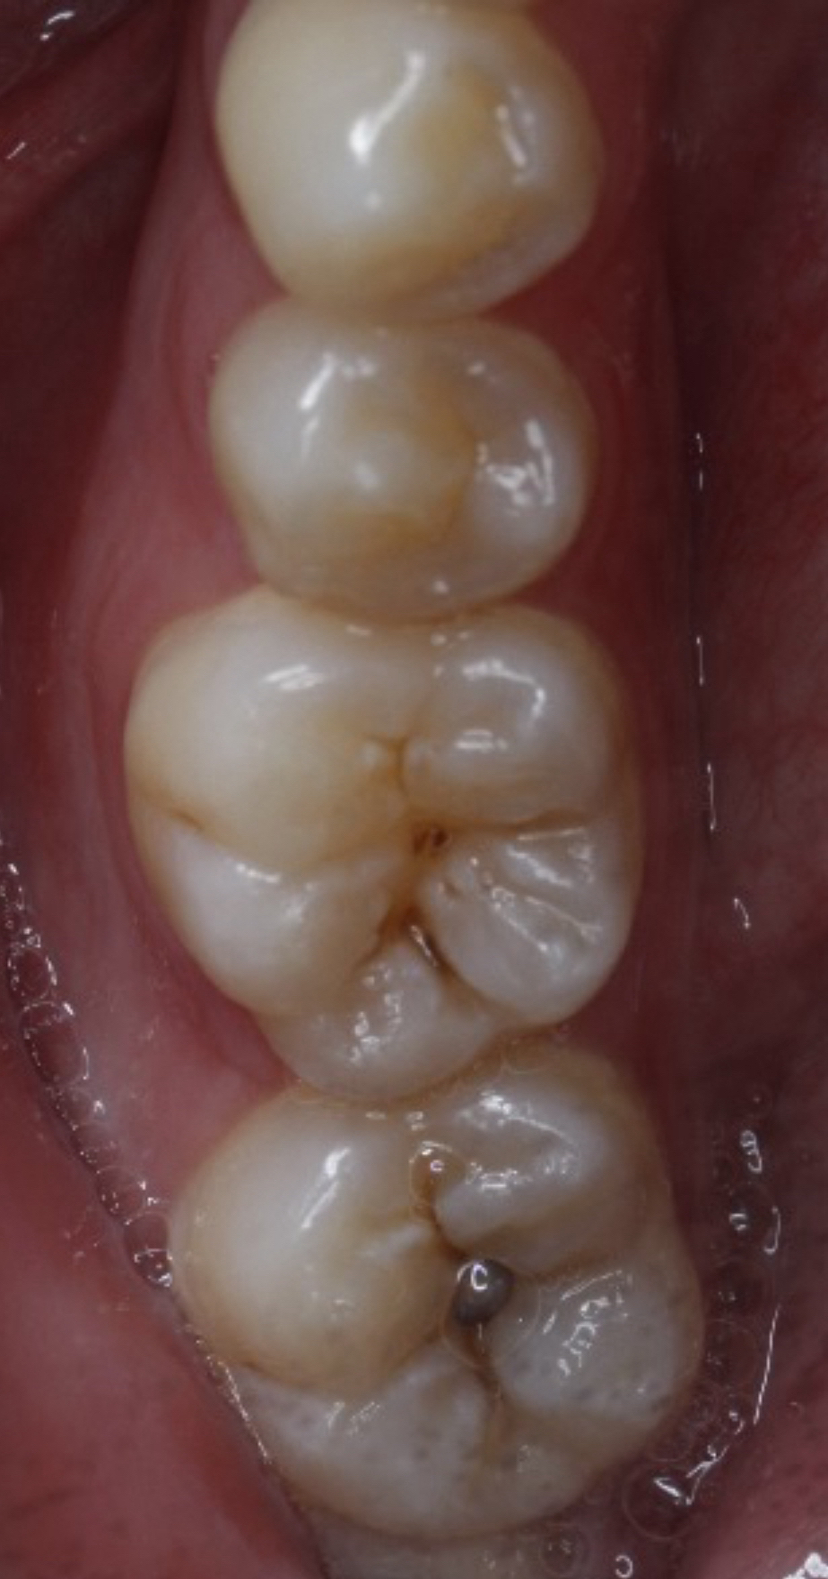

医生通过目视或X光片确定龋坏范围和深度。

用牙钻或激光去除蛀坏部分,确保剩余牙齿结构健康。

清洁窝洞后,填入补牙材料(如树脂、玻璃离子等),塑形并固化。